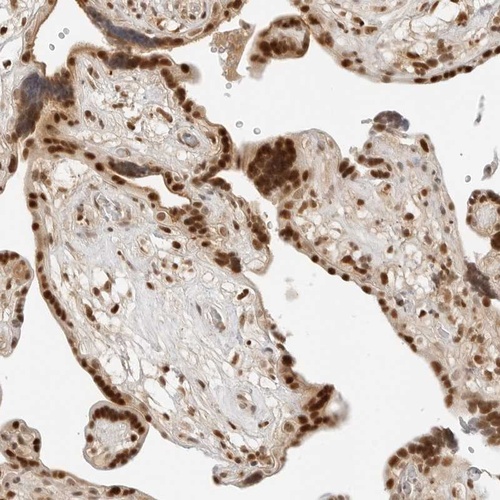

Immunohistochemical staining of human placenta shows strong nuclear positivity in trophoblastic cells.